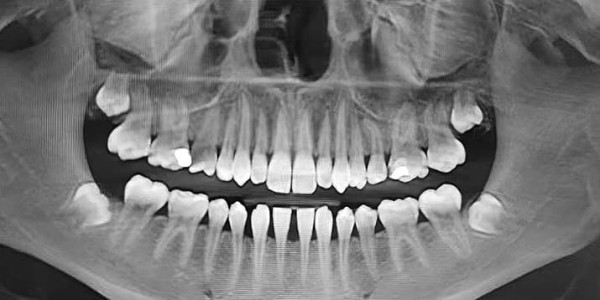

Специалист рассказал о стадиях формирования 8-х зубов, которые всегда следует учитывать при принятии решения об их удалении (см. рис. 1.): А — зачаток зуба, кальцификации нет, В — начальная кальцификация бугров, С — кальцификация бугров, D — начало кальцификации коронки, Е — полная кальцификация коронки, F — начало формирования корней, G — полное формирование корней, H — закрытие верхушечных отверстий корней.

Рисунок 1. Стадии формирования 8-х зубов по данным ортопантомографии.